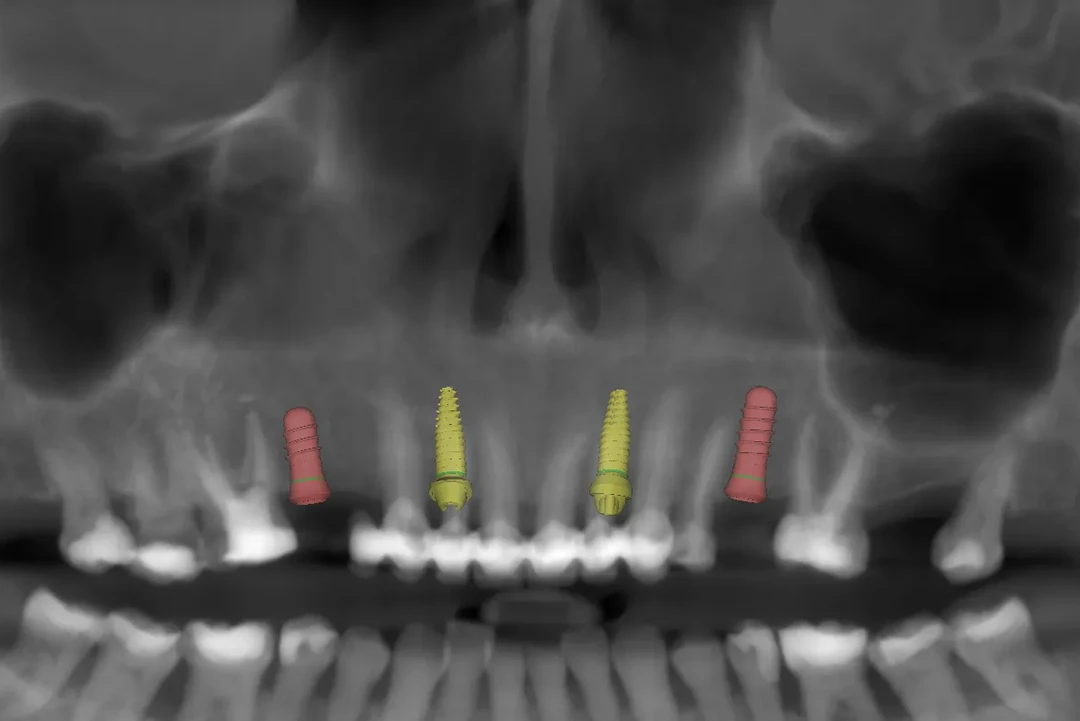

Somos Alzamora Dental, una clínica de referencia en Rubí especializada en cirugía guiada y carga inmediata, una técnica avanzada que permite colocar implantes dentales junto a una prótesis provisional en un solo día, siempre que el caso lo permita. Gracias a la planificación digital en 3D y al uso de una guía quirúrgica personalizada, la intervención es más precisa y mínimamente invasiva. Esto se traduce en menos tiempo de cirugía, menores molestias postoperatorias y una recuperación más rápida, con un resultado estético inmediato y altamente predecible.

✅ Precisión milimétrica en la colocación tridimensional ✅ Menor inflamación y recuperación postoperatoria más rápida ✅ Sonrisa funcional desde el primer día